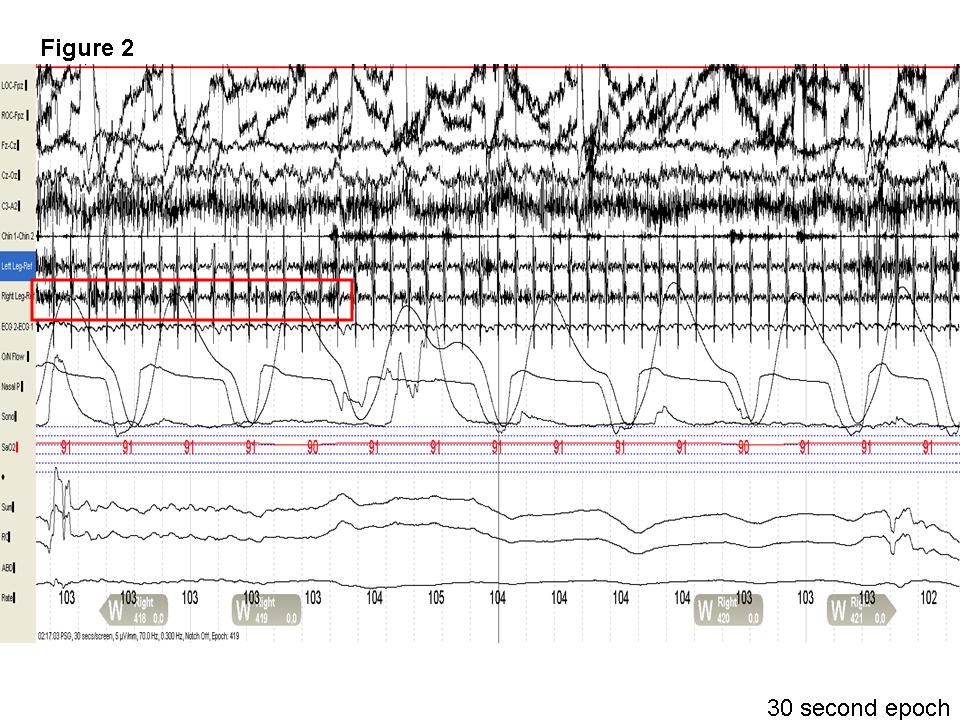

Discussion: Note the presence of recurrent right leg movements (left leg is covered by a sheet) in the first 10 seconds and the last 15 seconds of the video as the patient transitions from wake to stage N1 and in stage N1 respectively. Similarly, the 30-second epoch shows recurrent electromyographic (EMG) potentials at 1-2 Hz in the right leg with burst potentials greater than 250 milliseconds, lasting for longer than 10 seconds. This meets the criteria for hypnagogic foot tremors(1). Though alternating leg muscle activation (ALMA) is also a possible diagnosis, the surface EMG recorded activity (Figure 2) only from the right (indicated by the red box) and not from the left anterior tibialis muscle (highlighted by blue on figure 2). Of interest, periodic leg movements during wakefulness and not during sleep were also noted in our patient (Figure 3, red arrows).